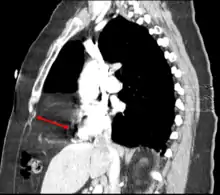

| Morgagni hernia seen on a chest radiograph. | |

This rare anterior defect of the diaphragm is variably referred to as a Morgagni, retrosternal, or parasternal hernia. Accounting for approximately 2% of all CDH cases, it is characterized by herniation through the foramina of Morgagni which are located immediately adjacent and posterior to the xiphoid process of the sternum.[4]